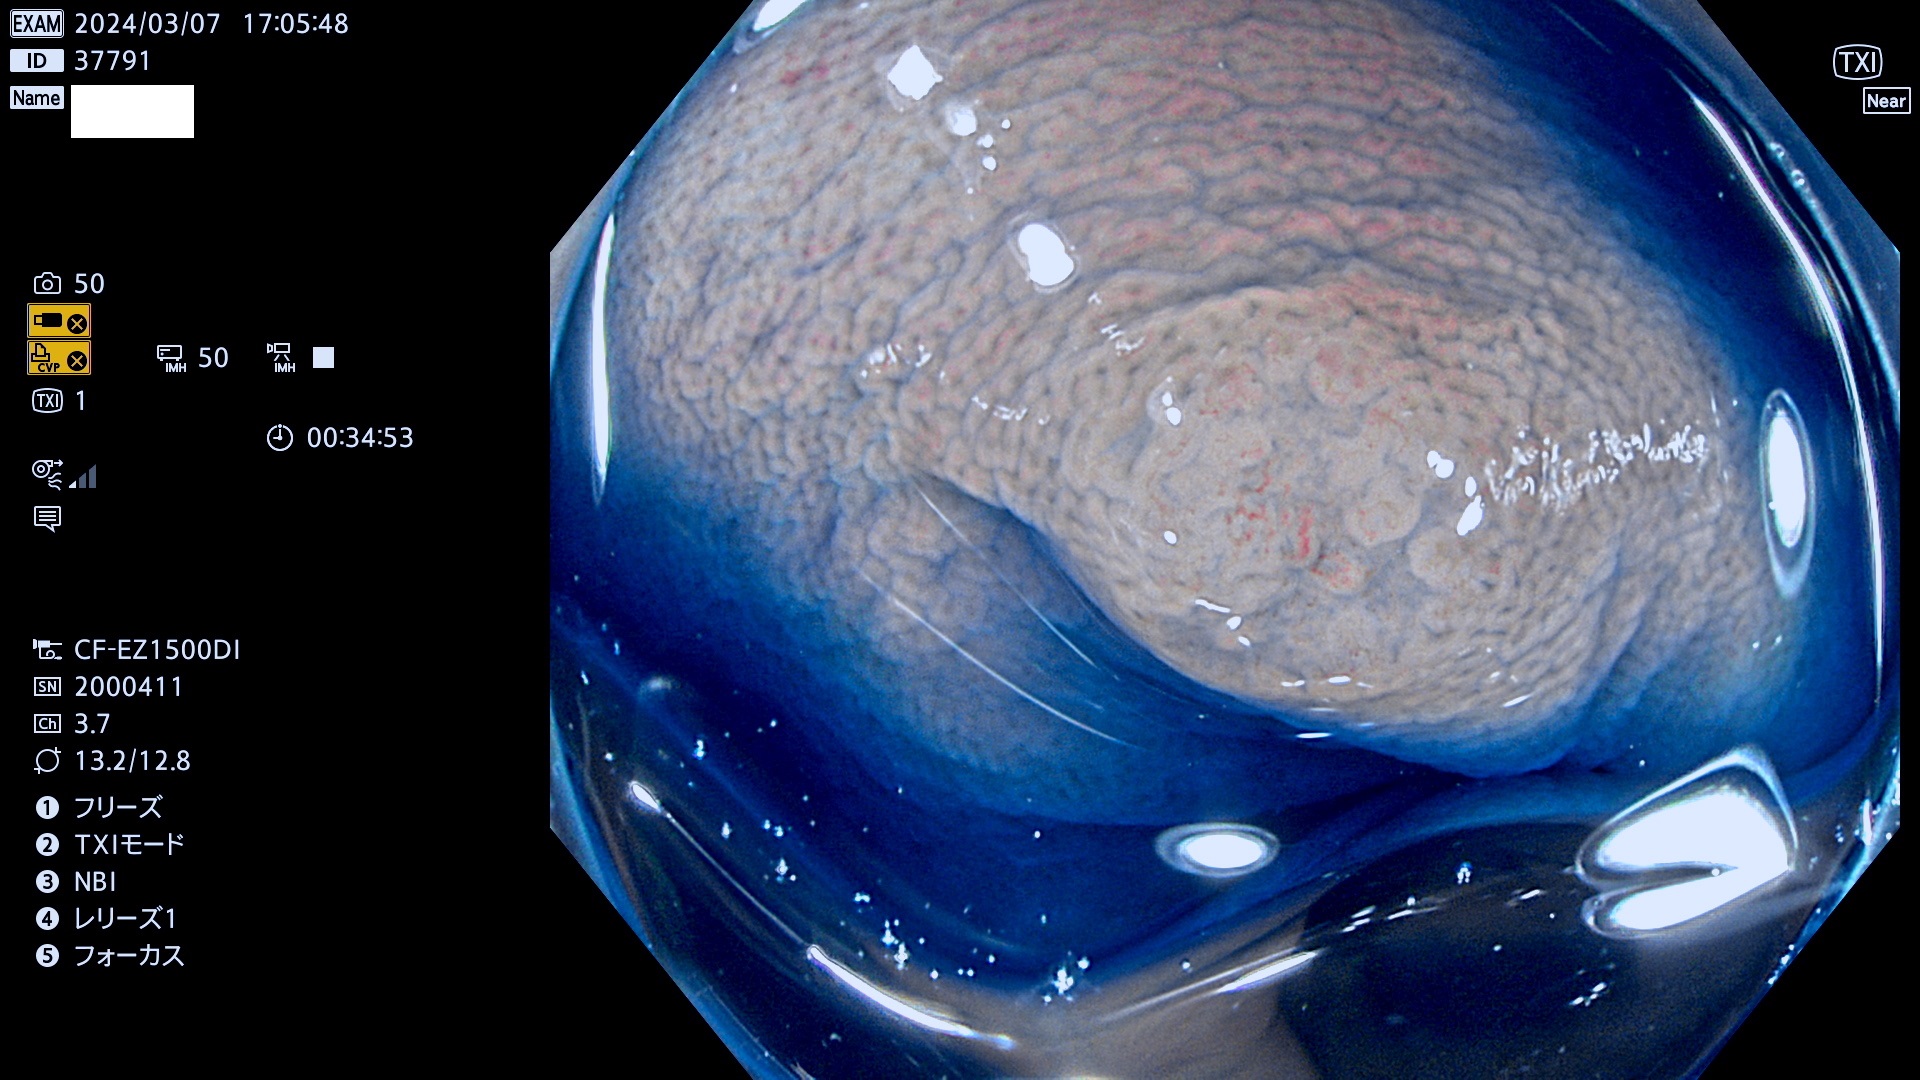

今週のUb、Uc型腺腫

表面型腺腫(Flat Adenoma)の中で、完全に平坦な物をUb、陥凹している物をUcと呼びます。平坦隆起型(Ua)よりも、発見が難しく危険な病変です。

毎週の検査(木・金・土・日)に発見されたUb、Uc型・腺腫を、その週の日曜の夜にUPし1週間、提示します。

抽出の対象期間 2024年3月7日(木)〜3月10(日)の4日間(40件の検査)6件 (6/40=13%)